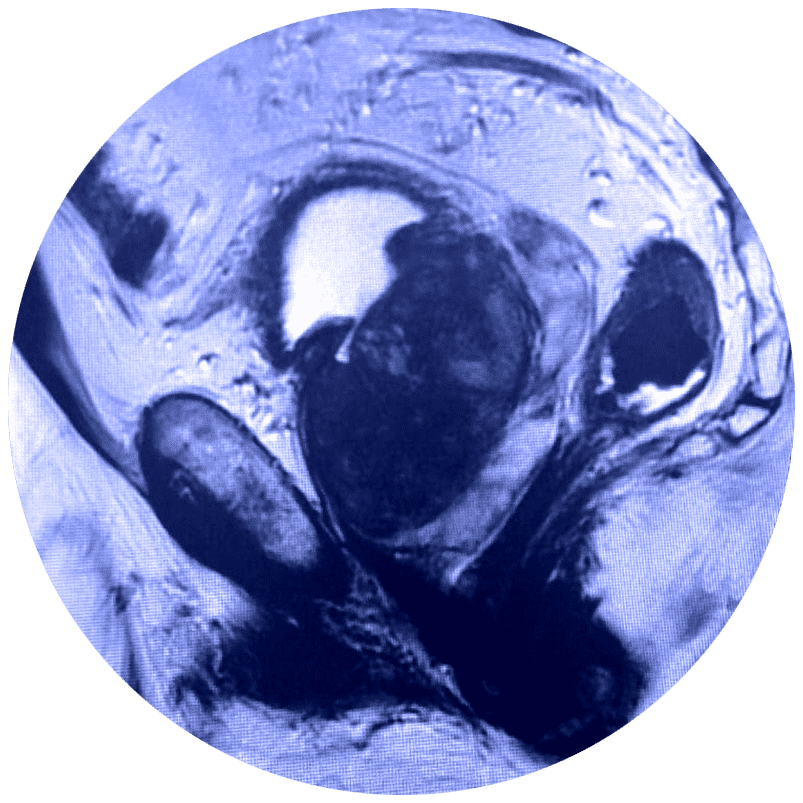

El estudio de Resonancia Multiparamétrica de Próstata no requiere de exposición a la radiación, evalúa el movimiento de las moléculas de agua (denominado difusión del agua) y el flujo sanguíneo (denominado imágenes de perfusión) adentro de la próstata. Esto ayuda al médico a diferenciar entre el tejido enfermo y el tejido sano de la próstata.

El médico utiliza la RMN para evaluar el cáncer de próstata y ver si se encuentra confinado a la próstata. La Mp-MRI proporciona información acerca de las moléculas de agua y del flujo sanguíneo a través de la próstata. Esto ayuda a determinar si el cáncer se encuentra presente y, si es el caso, si es agresivo y si se ha diseminado.